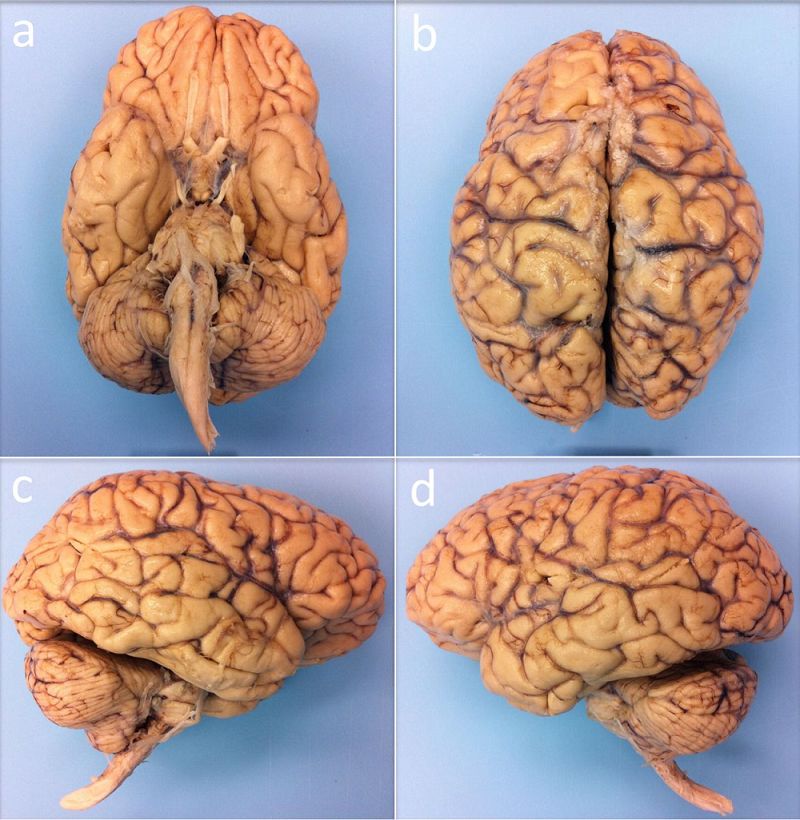

为了获得一份完整且详细的大脑三维图像,波士顿麻省总医院及其它地方的研究人员,将目标锁定在一名死于病毒性肺炎的 58 岁女性大脑标本,其大脑重达 1210克(正常范围 1200 至 1500 克),死后 14 小时一直固定在 10% 的福尔马林中。

图 | 体外核磁共振成像的人脑标本,下方(a)、上方(b)、右侧(c)和左侧(d)角度(来源:B.L. EDLOW ET AL/BIORXIV.ORG 2019)

而且这个来自捐献的大脑样本被认为是健康的,因为该女性没有神经系统疾病病史,死于非神经病因。

在扫描开始之前,大脑标本已经在固定剂中保持了 35 个月,之后研究人员将大脑标本放入一个定制的球形聚氨酯盒子,以让大脑保持静止并让干扰的气泡逸出。